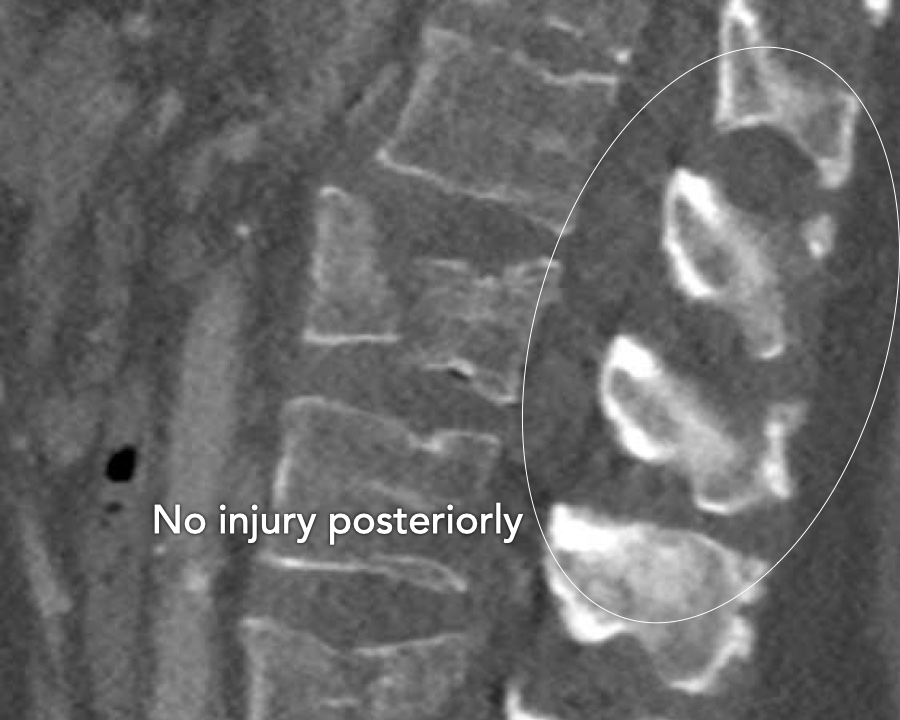

What is the AO-type of the vertebral body fracture based on only these two inages?

Findings:

- Fractures of the vertebral body with involvement of upper endplates (1 points) and posterior wall (2 points)

- Bulging of the posterior wall without any other signs of dislocation is the result of the burst fracture.

Therefore no C injury.

Conclusion

Injury type A3